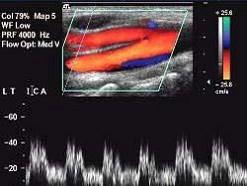

如图所示,该频谱为下列那支血管的频谱特点?(?)A.颈外动脉B.颈内动脉C.颈总动脉D.颈内静脉E.椎动脉

问题 如图所示,该频谱为下列那支血管的频谱特点?(?)

选项 A.颈外动脉 B.颈内动脉 C.颈总动脉 D.颈内静脉 E.椎动脉

答案 B